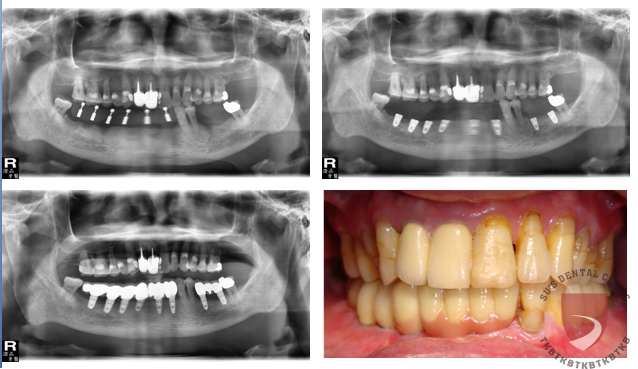

全口重建邱xx

成效因人而異,須遵從專業醫師指引